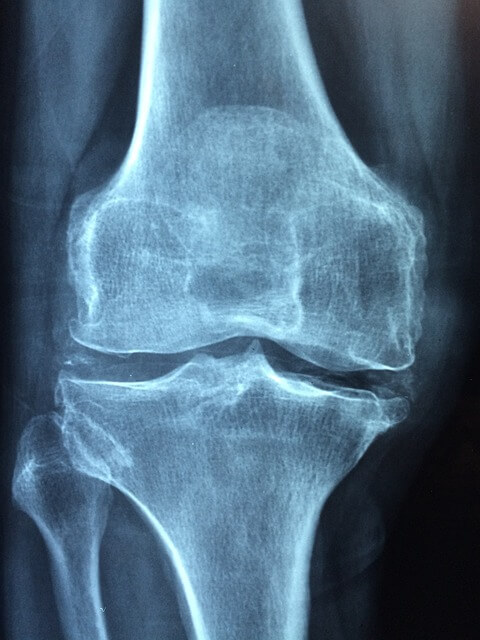

1. 관절 건강 증진: 콘드로이친은 연골의 구성 성분으로, 관절 강직과 손상을 막는 데 도움 됩니다. 또한 연골 조직의 천연 스펀지 역할을 해 원활한 관절 움직임에 기여하며 관절 내 충격 흡수능을 증진시킵니다.

2. 연골 손상 예방: 콘드로이친은 인체 내에서 연골의 탄력을 높이고 주기적인 새로운 세포 생성을 도와 손상된 연골을 회복시키며 추후 손상을 예방하는 데 도움이 됩니다.

3. 관절염 증상 완화: 콘드로이친이 관절 염증과 통증을 줄이는데 도움을 주며 특히 고관절염, 무릎관절염 등 관절염 환자에게 효과적입니다. 글루코사민과 함께 사용하면 더욱 효과적인 증상 완화가 기대됩니다.

4. 통증 감소: 콘드로이친 복용으로 인한 통증 완화 효과가 뚜렷한 것으로 알려져 있습니다. 수술 못지않은 효과를 거둔 예도 있습니다.

5. 관절 윤활제 생성 촉진: 콘드로이친은 인체에서 자연으로 생성되는 관절 윤활제의 생성을 촉진하며 연골과 뼈 마모를 줄이고 관절의 원활한 움직임을 지원합니다.

6. 연골 재생: 노화로 인한 연골 손상이 증가할 수 있으나 콘드로이친을 섭취해 나이가 들어도 연골의 손상을 줄이고 건강한 관절 상태를 유지할 수 있습니다.